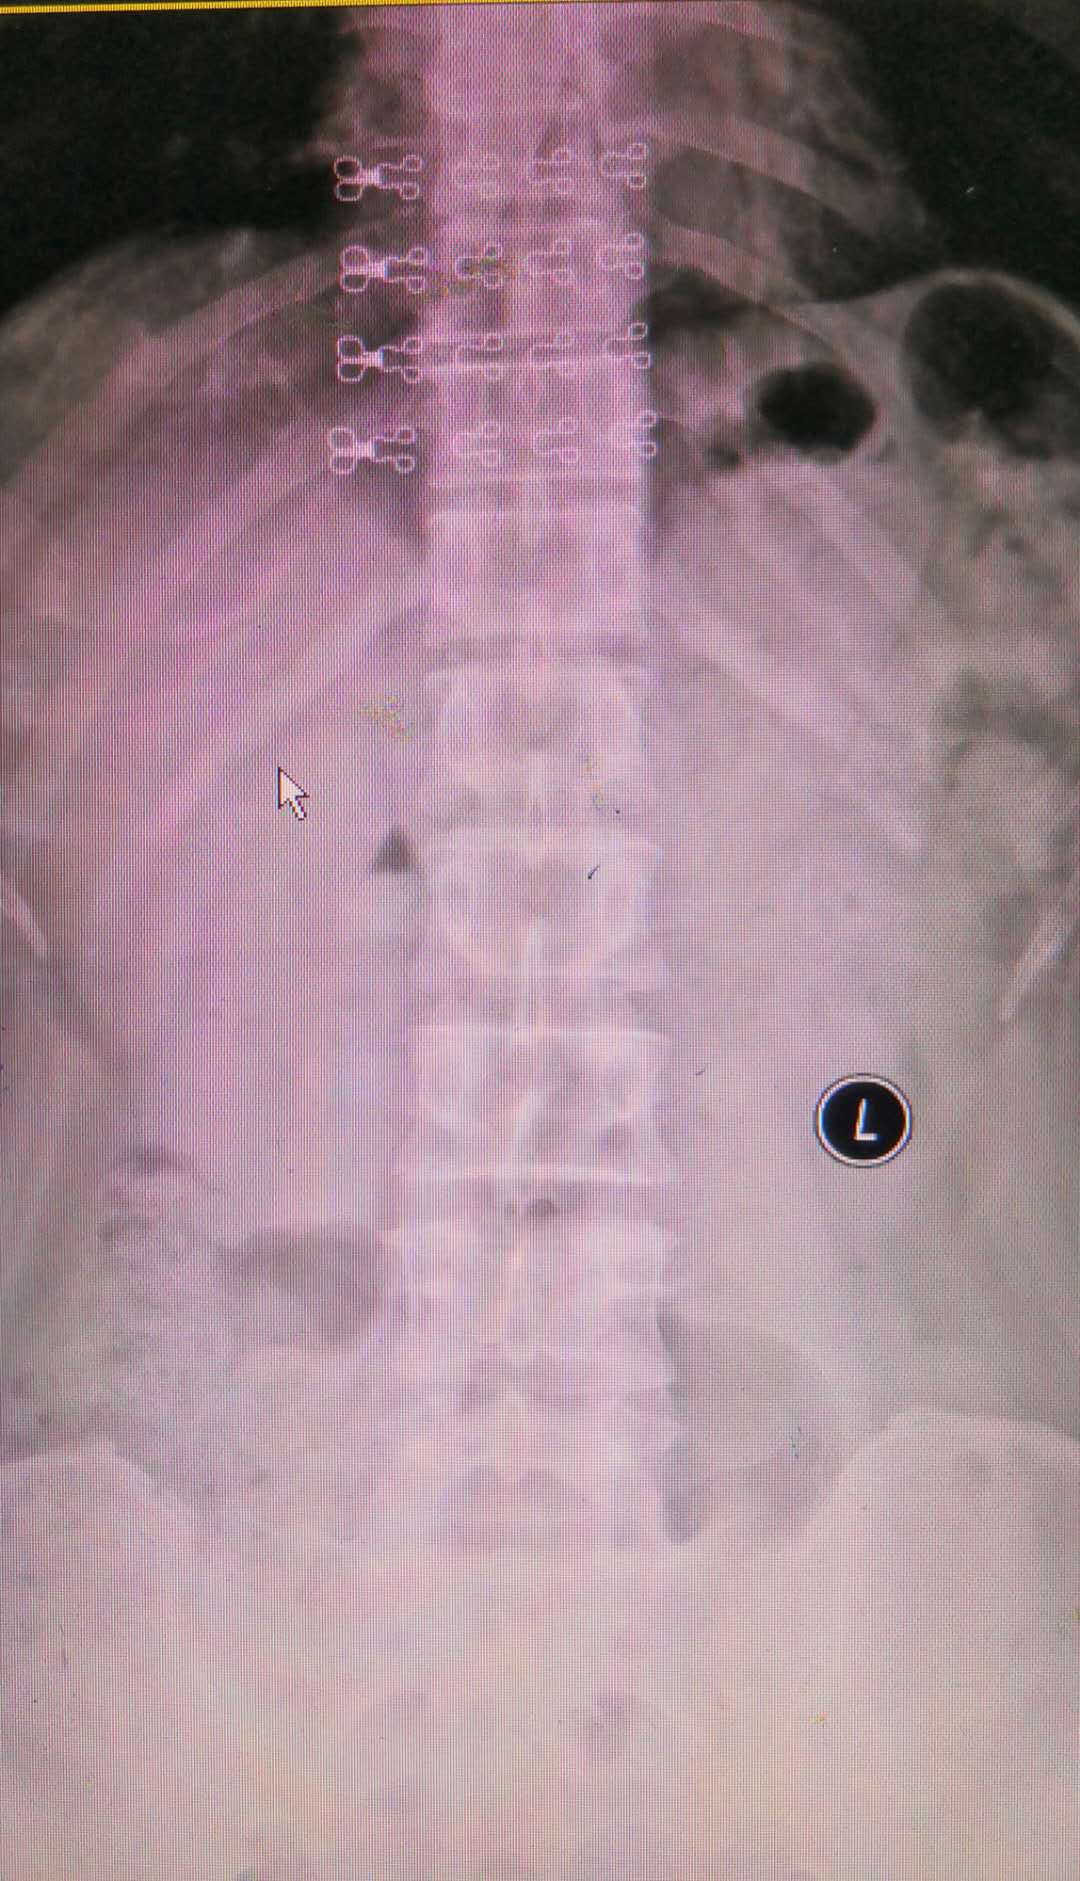

人体正常的腰椎排列顺序是有正常的生理曲度,但排列比较整齐;有些人由于先天的峡部不连、畸形或者后天的发育不良,退变等各种原因引起其中的一个腰椎相对于下一个椎体向前滑移动,这就是我们所说的“腰椎滑脱”如下图所示正常的腰椎正侧位图:

腰椎的生理曲度存在,排列整齐,只是稍有退变